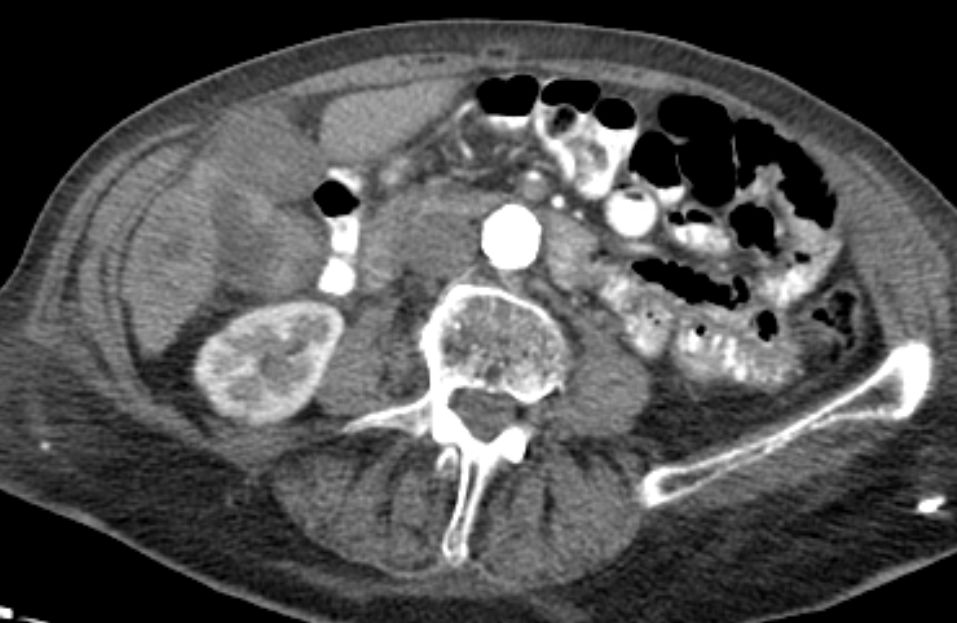

Lebermetastase |

86-jähriger Mann, bei dem vor 9 Monaten eine Cholezystektomie wegen gedeckt perforierter Cholezystitis vorgenommen wurde. Jetzt Verdacht auf Leberabszess. Die laparoskopische Biopsie ergab ein Adenokarzinom. Die Nachbefundung der Gallenblase erbrachte immunhistochemisch den Nachweis eines Gallenblasenkarzinoms. | ||